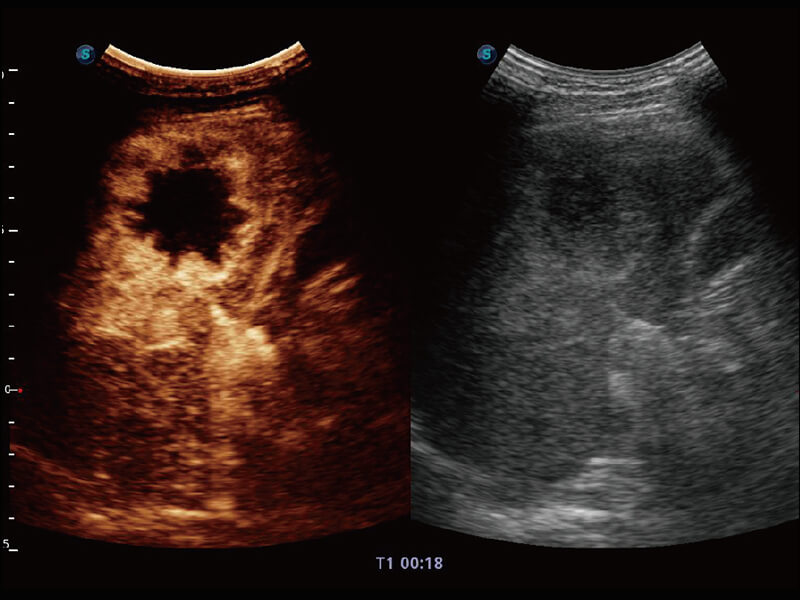

高分辨率容积成像 栩栩如生

超宽频带技术,为容积成像带来优质的二维图像基础,为您呈现丰富的结构细节,栩栩如生地展示宝宝的宫内形态以及各种组织的立体结构。